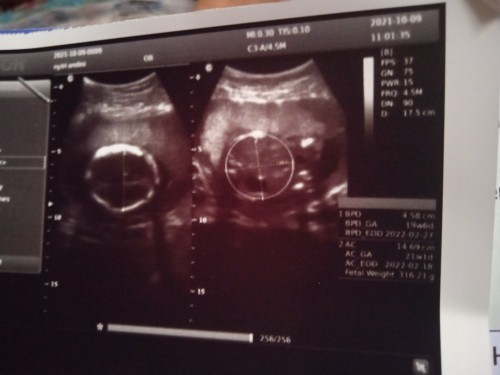

Salam kenal bunda bunda semua. Aku mau tanya. Tgl 9 oct kmren aku kontrol kehamilan dan USG. Kau cma d periksa sebentar bgt sm bidannya . Tau2 udahan Padahal mau nnya bnyk. Mau nnya kan ga enak dokternya uda blg selesai. Cma nnya jk nya uda keliatan blm. Katane blm, masih kecil. Tapi pulang2 aku malah nyesel dan malah jadi kefikiran. Soale tkt ukuran dedenya ga sesuai. Bunda2 yang tau atau nakes boleh info gak. Ini ukiran dede ku uda sesuai atau belum. Soalnya klo di aplikasi dan kau baca di google. Ukuran kepala. Paha sm bbj nya ga sesuai. Aku takut bgt 😭 Ini rinciannya. Semoga bunda bunda disini bisa bantu aku ya. Biar gak kefikiran huhu FPS : 37 GN : 75 PWR 15 FRP 4.5M DN 90 D 17.5 BPD 4.58 CM BPD GA 19 W6D BPD EDD 22 FEB 2022 AC 14.69 CM AC GA 21W1D AC EDD 18 GEB 2022 FW 316.21G #seriusnanya #bantusharing #ingintahu #pleasehelp #firstbaby #1stimemom